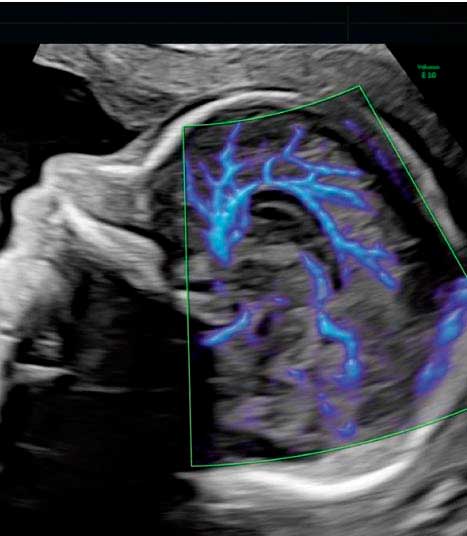

Somos expertos en detección temprana de anomalías. Brindamos una gama completa de Ultrasonidos Fetales y Ecografías 5D-7D: